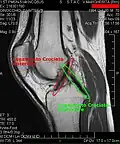

Both anterior cruciate ligament (ACL) and posterior cruciate ligaments (PCL) are hypointense on both T1 and T2 weighted images of MRI. However, some high signal striations are often seen at the distal part of the ACL, making ACL higher intensity than PCL on MRI scans.[20]